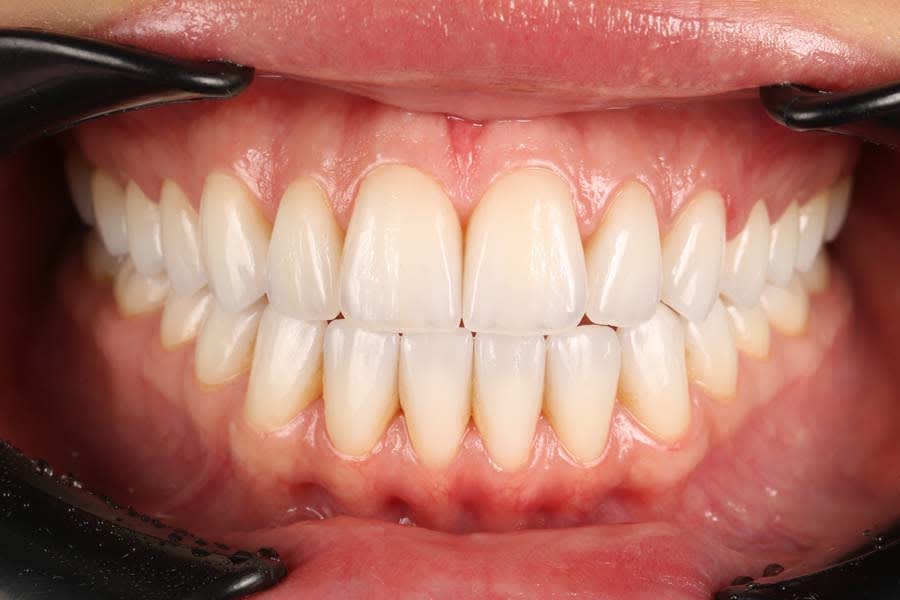

Treatment eliminated the anterior open bite, restored functional occlusion, and achieved harmonious esthetics matching the approved design (Figure 14). Final restorations showed precise proximal contacts and stable margins and required no occlusal adjustments. The multilayered lithium-disilicate restorations closely replicated natural teeth in form, color, and light dynamics.11

The esthetic result achieved anterior tooth symmetry, correct midline position, shape and proportion consistent with the approved wax-up, and individual effects like opalescence, incisal translucency, and natural halo. The patient reported significant improvement in smile esthetics, increased social confidence, and functional satisfaction. Clinical documentation confirmed no inflammatory changes at the gingival margin, stable soft tissues along the prosthetic structures, and preserved papilla height.

At 1-year follow-up, the gingival contour remained stable with no inflammation, recession, or discoloration of restorations. The long-term stability of the esthetics and function reflected the quality of the material choices and protocol adherence.13 Functional parameters were maintained, including no occlusal interferences, stable CR, and balanced lateral contacts. The patient continued using a custom nightguard to prevent potential parafunctional forces. The esthetic result, which remained unchanged after a year, demonstrated restoration durability, biocompatibility, and an effective protocol.

Final photographs showed smile harmony, optimal anterior tooth display, symmetry, and balanced soft- and hard-tissue relationships (Figure 15). The achieved outcome aligned with the initial clinical and esthetic goals and required no further corrections. The case demonstrated successful management of a complex open-bite rehabilitation through a multidisciplinary approach, digital modeling, and integrated functional diagnostics.